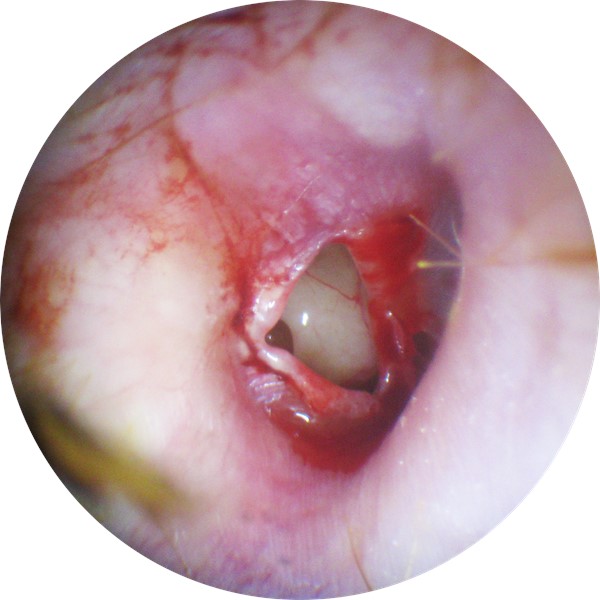

| LEVEL | DESCRIPTION | PICTURE |

| TEED 0 | Normal tympanic membrane. No evidence of injury despite the presence of symptoms. |

|

| TEED 1 | Diffuse redness and retraction of tympanic membrane. Erythema over part of the tympanic membrane due to inflammation, particularly around the manubrium. |

| TEED 2 | Diffuse redness and retraction of tympanic membrane, plus slight hemorrhage within the tympanic membrane. |

| TEED 3 | Diffuse redness and retraction of tympanic membrane, plus gross hemorrhage within the tympanic membrane. |

| TEED 4 | Dark and slightly bulging tympanic membrane due to free blood in the middle ear (a fluid level may also be present). |

| TEED 5 | Free hemorrhage into the middle ear, tympanic membrane perforation;  blood may be visible outside or within the external auditory canal. |